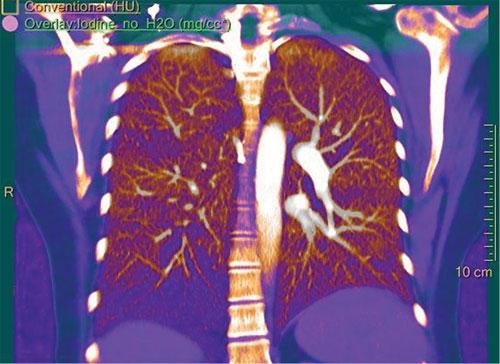

A low dose computed tomography (CT) pulmonary artery angiography examination was performed using the IQon Spectral CT, with subsequent spectral data review and analysis.

The conventional 120 kVp image demonstrates filling defects in the segmental and subsegmental vessels of the right lower lobe. There is no evidence of consolidation or infarction.

The iodine and effective Z images demonstrate iodine perfusion defects in the right lower lobe that correlate to the filling defects in the conventional 120 kVp images. These findings confirm the differential diagnosis of a pulmonary embolus.